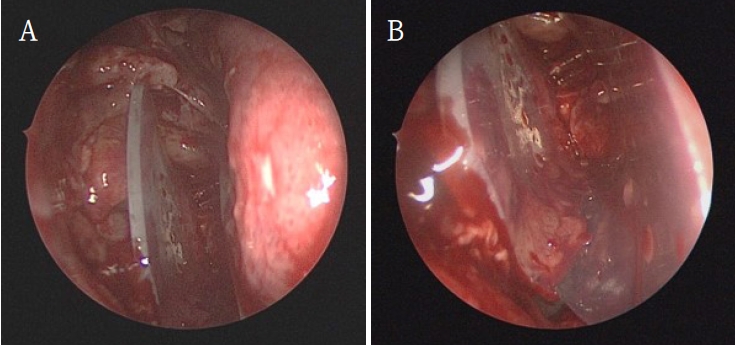

Subsequently, the oral and maxillofacial surgery team performed intraoral access for reconstruction of the orbital floor. A vestibular incision approximately 3 cm in length was made, extending from the left canine to the first molar region. A bony window measuring approximately 15 × 10 mm was created in the anterior wall of the maxillary sinus to provide direct visualization of the inferior orbital wall defect. Herniated orbital tissue was carefully repositioned into the orbital cavity, and the orbital floor was anatomically reconstructed. A titanium miniplate with screws (DePuy Synthes, Oberdorf, Switzerland) was applied across the fracture line to achieve rigid fixation (Fig. 4). Layered closure was then performed to ensure proper wound healing and anatomical restoration.

Transantral reconstruction of the inferior orbital wall. A. Intraoral transantral approach exposing the inferior orbital wall defect. B. Titanium miniplate fixation across the orbital floor fracture.